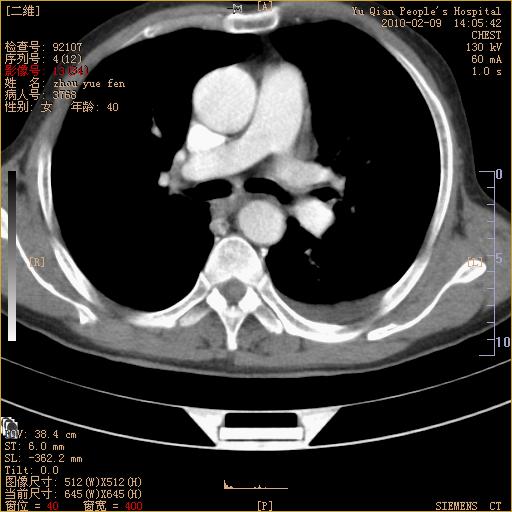

男性,73岁,咳嗽咳血数天,诊为肺ca伴左肺下叶后段阻塞性炎症、肺不张妥否?

右下肺有转移?

左下肺中央型肺癌伴结段形肺不张,左侧胸腔积液,纵隔内见部分增大淋巴结(反应性增生或转移)

左下基底干支气管明显变窄。

左肺下叶基底段支气管狭窄,左肺门增大,左肺下叶团片状病灶。中心型肺癌伴柱塞性炎症可能大,建议支气管镜检查。

左下肺中央型肺癌伴节段性肺不张,左侧胸腔积液,纵隔内见肿大淋巴结

左下基底段支气管变窄。建议进一步纤支镜检查。

1、左肺下叶后基地段肺癌伴阻塞性炎症,左下肺门淋巴结转移。2、左侧胸腔积液。